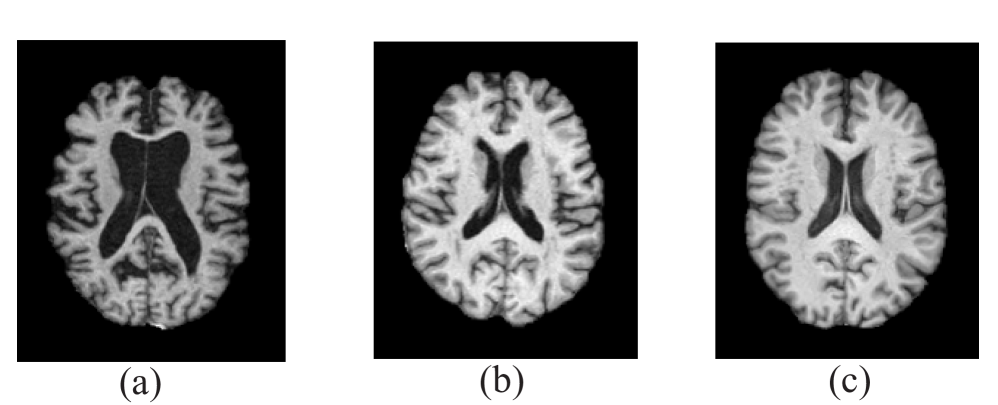

In this work, we used data from the Alzheimer’s Disease Neuroimaging Initiative (ADNI)111http://adni.loni.usc.edu. ADNI was launched in 2003 as a public-private partnership, led by Principal Investigator Michael W. Weiner, MD. The primary goal of ADNI has been to test whether serial MRI, positron emission tomography (PET), other biological markers, and clinical and neuropsychological assessments can be combined to measure the progression of mild cognitive impairment and early Alzheimer’s disease. We utilized 2010 subjects, all T1-weighted MRI volumes available in the ADNI1, ADNIGO, ADNI2, and ADNI3 phases at the time of our experiments. Table 1 presents the detailed demographics and clinical information of the included subjects. While multiple MRI scans are available for most subjects, representing time series data, we used only the baseline visit volumes of each subject for consistency. Sample images from each of three classes are illustrated in Fig. 4. Although we tried to select and display images with obvious differences in each of the categories in Fig. 4, the difficulty of distinguishing between MCI and CN cases is evident, which presents a significant challenge for diagnosis and model training in three classes. Atrophy in the GM and hippocampal regions of the medial temporal lobe are among the most noticeable effects of Alzheimer’s disease [37].

Figure 4: A sample slice of axial plane from ADNI for each class of Alzheimer’s disease diagnosis. (a) AD. (b) MCI. (c) CN.